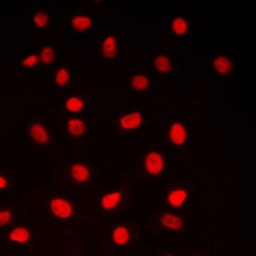

ICC/IF analysis of formalin-fixed MCF7 cells using GTX56252 CREB antibody.

Red : Primary antibody

Blue : DAPI

Permeabilization : 0.1% Triton X-100 in TBS for 5-10 minutes